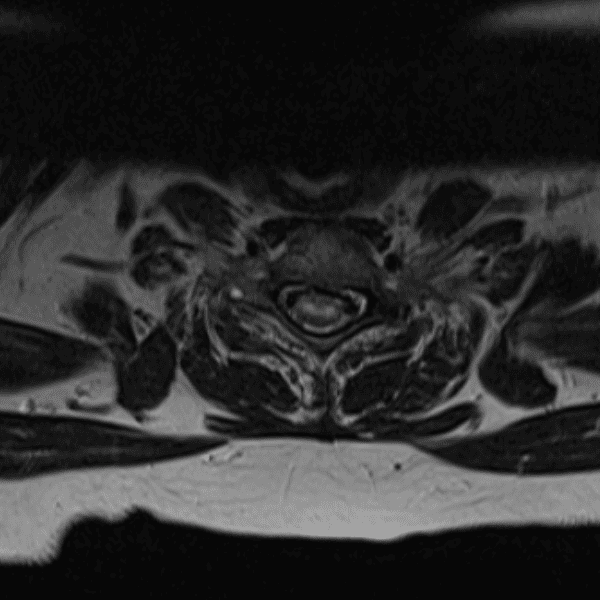

Simulates call by including subtle or difficult cases and some normals.

35 cases